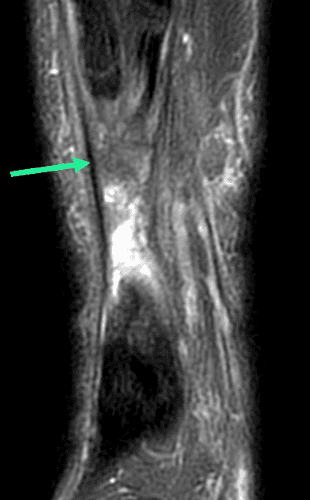

Douleur aiguë de l'arrière-pied chez un patient de 70 ans lors d'un changement de direction brutale pendant la marche.

MRI